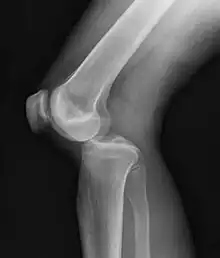

| Plain lateral X-ray of the left knee showing a posterior knee dislocation[1] | |

Plain X-rays, CT scan, ultrasonography, or MRI may help with the diagnosis.[2][11] Findings on X-ray that may be useful among those who have already reduced include a variable joint space, subluxation of the joint, or a Segond fracture.[5]

They may be divided into five types: anterior, posterior, lateral, medial, and rotatory.[4] This classification is based on the movement of the tibia with respect to the femur.[11] Anterior dislocations, followed by posterior, are the most common.[2] They may also be classified on the basis of which ligaments are injured.[2]